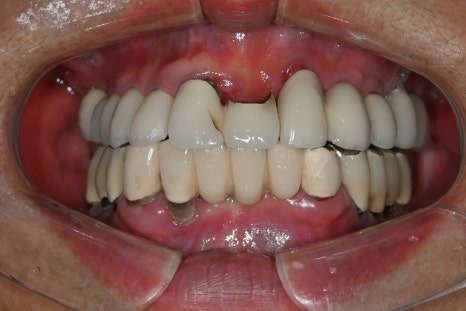

치료 전

치료 후

위와 같이 앞니 임플란트 치료를

잘 마친 환자분께서

위 환자분은 부러진 앞니를

발치하고 임플란트를 즉시 식립했으며

디지털 방식으로 제작한

임시치아를 당일에 끼워드렸던 분으로,

당일 제작한 디지털 임시치아

전체 치료기간이 2개월이 채 걸리지 않아

매우 만족하시고

많은 분들을 소개해주신 분이었습니다.